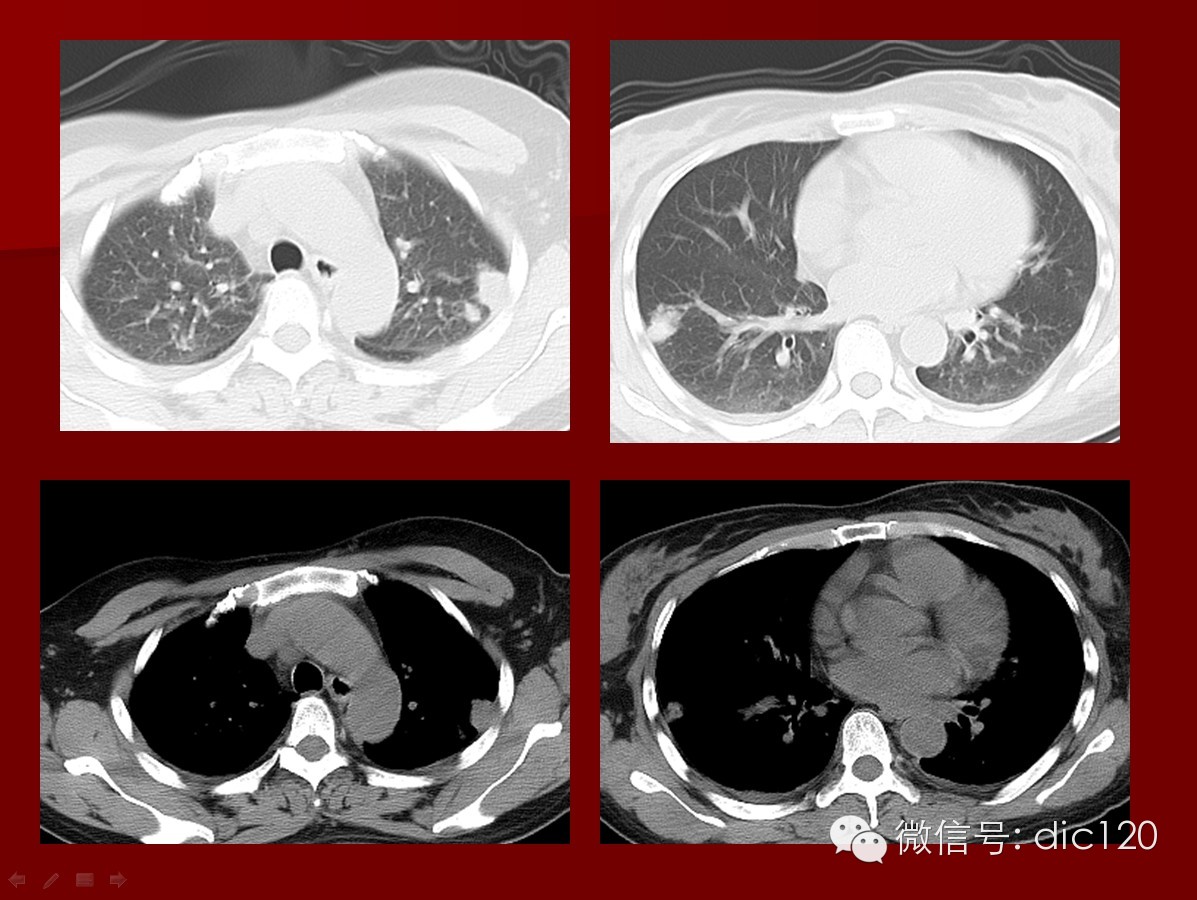

本病影像肺内表现特征:1)结节、球形肿块及空洞:病灶可单发也可多发,病灶多见于两肺下叶,也可位于肺尖,且肺外带好发,2/3病例球形肿块内出现空洞,洞壁较厚、不规则,其中可见液平,用免疫抑制剂及肾上腺皮质激素治疗,病灶可缩小或消失,病情恶化时可出现新病灶。斑片状影:较为少见,为肺血管炎引起的肺出血和肺梗死,合并炎症也可出现,病灶较大可占据一个肺段,病灶可在1~2周内缩小或消失,但又可出现新的病灶。